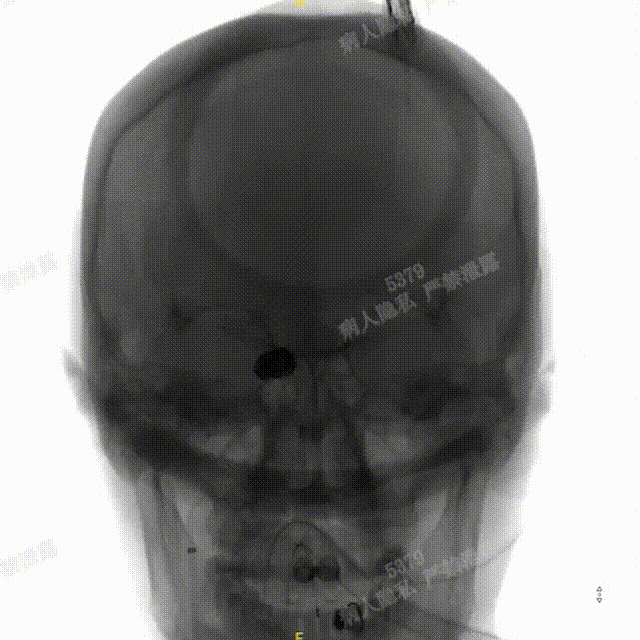

术中DSA造影:左侧颈内动脉正、侧位及3D造影,显示左侧颈内动脉后交通段动脉瘤。

术中DSA造影:右侧颈总动脉3D造影及右侧锁骨下正位造影。